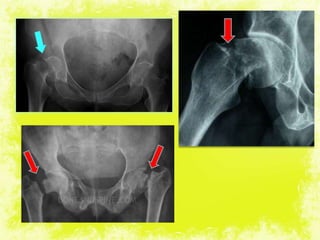

IMPACTED

UNDISPLACED

DISPLACED

Transepiphyseal

fracture

Inter trochanteric

Sub

trochanteric

Transcervical